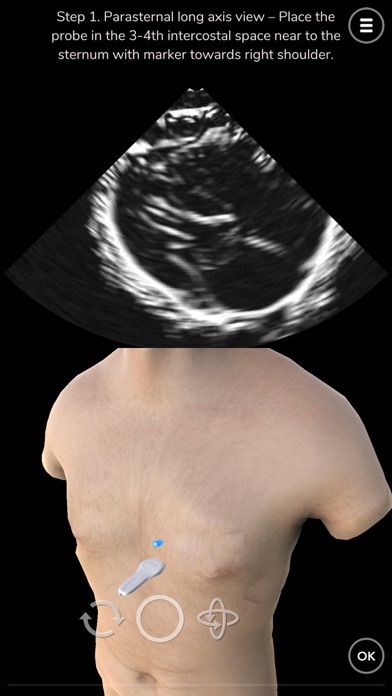

Learn ultrasound in a virtual ultrasound simulator. Deepscope ultrasound virtual learning modules are created to help learn the techniques of ultrasound.

-Basic ultrasound or sonogram probe movement

-Techniques for performing echocardiography or echo

The ultrasound simulator uses advanced computer graphics techniques simulate sound waves. The sonogram is created as a result of these simulations.